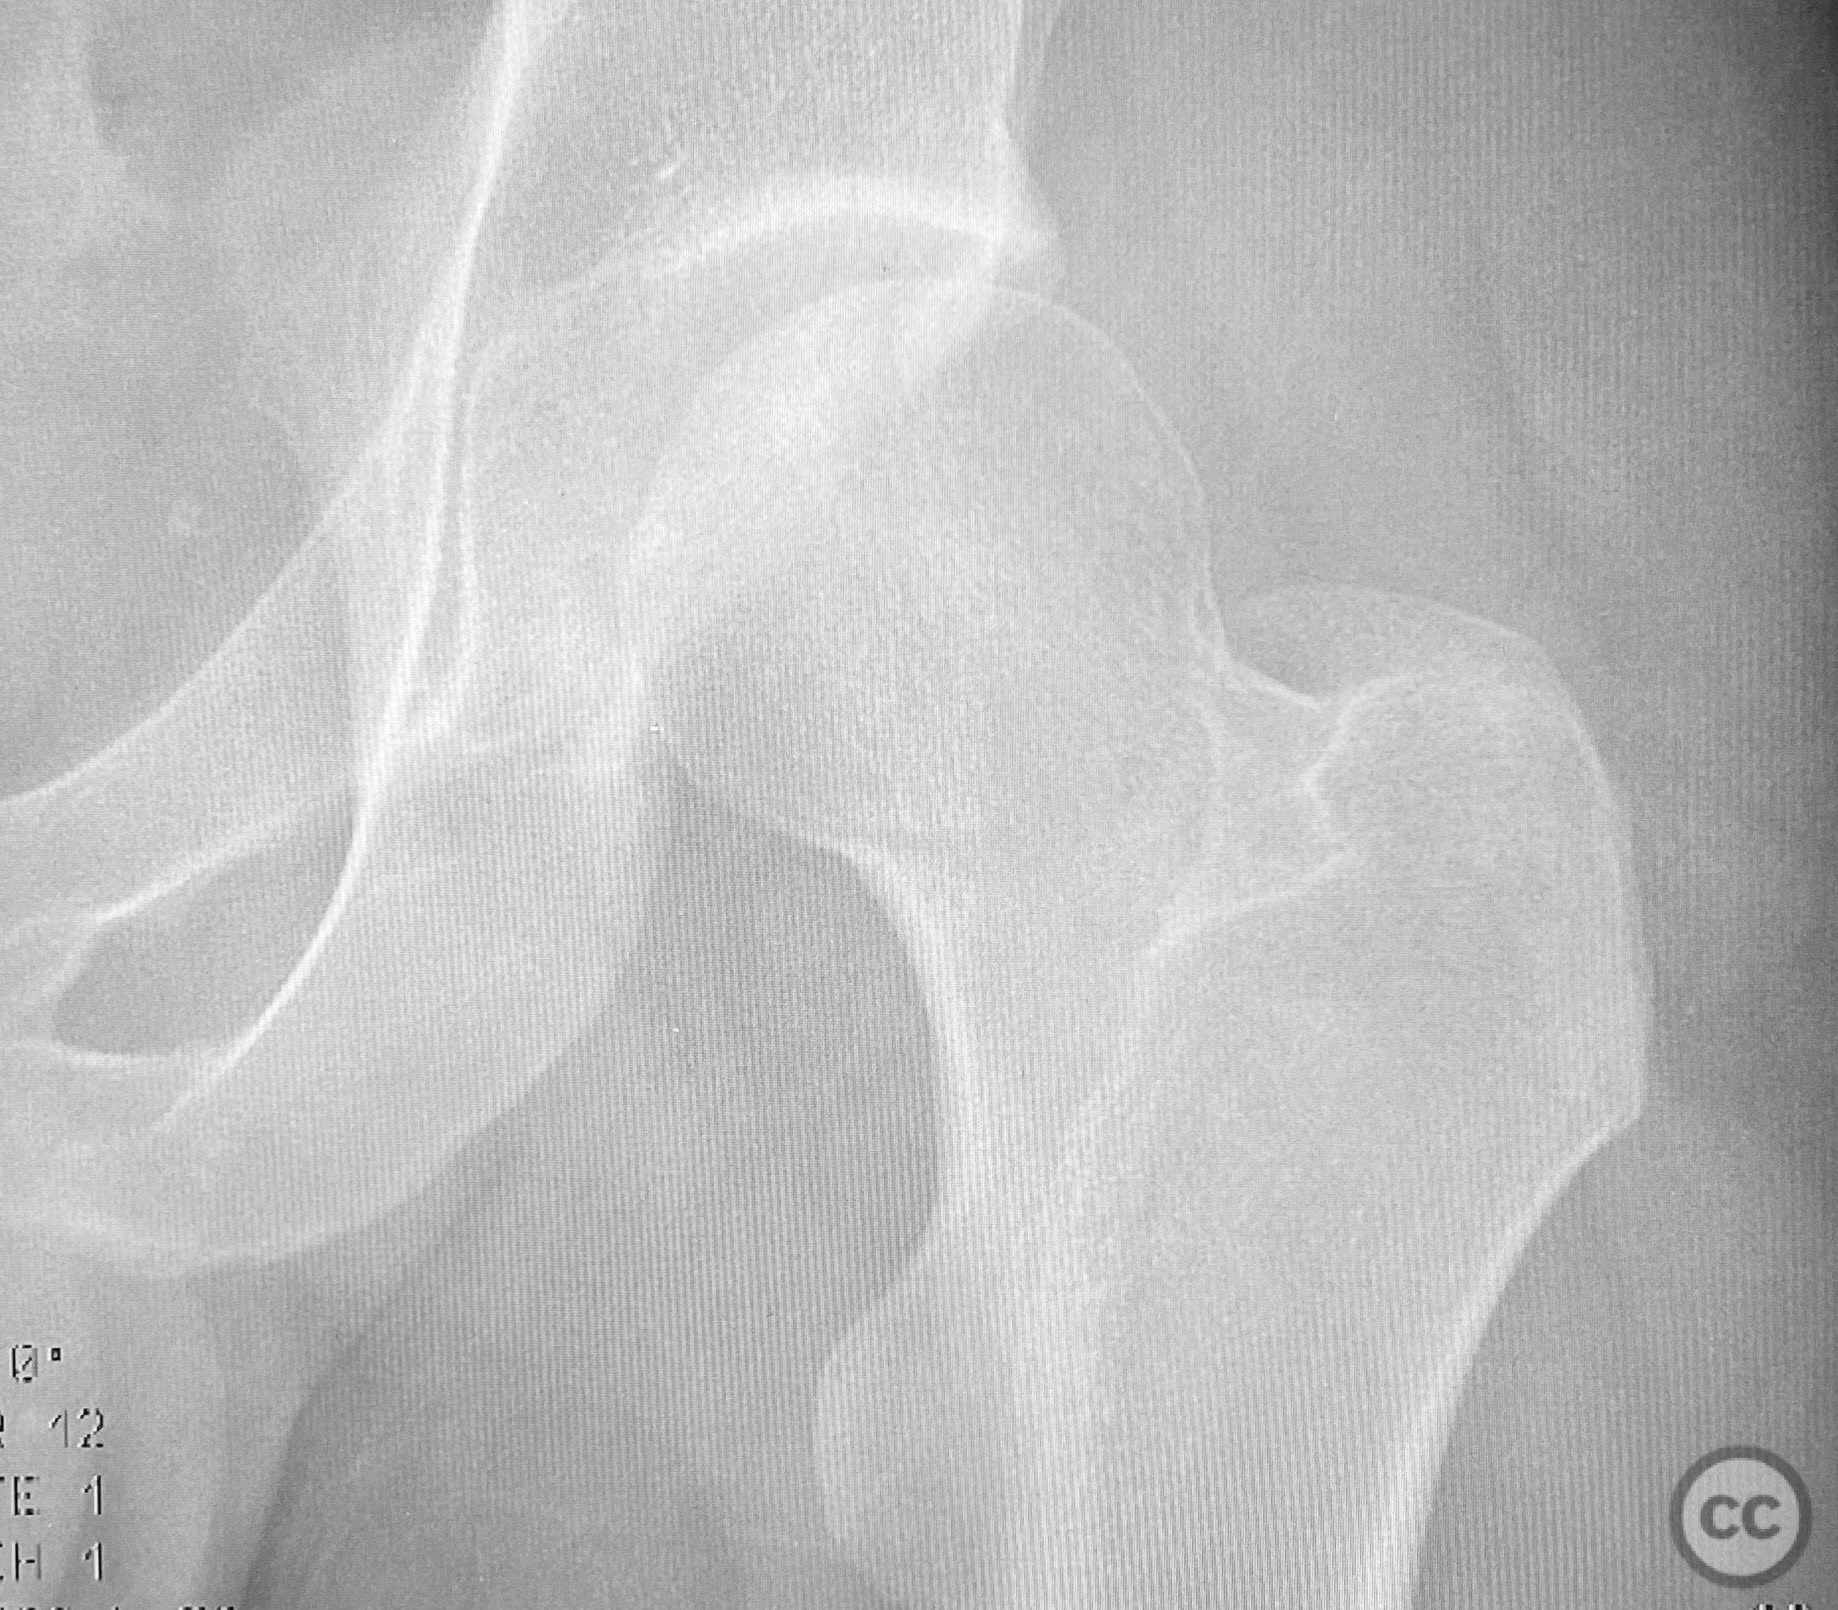

Clinical and radiological findings:  A patient involved in a motor vehicle collision presented with left hip pain exacerbated by any attempted movement. Initial axial and surface-rendered computed tomography (CT) imaging demonstrated an essentially nondisplaced posterior wall (PW) acetabular fracture (AO/OTA 62-A1.1). However, the anteroposterior (AP) scan image and coronal reconstructions revealed significant hip joint asymmetry. Examination under anesthesia with fluoroscopic guidance confirmed persistent joint incongruity, with the femoral head subluxating posteriorly at 50–60 degrees of flexion. A pure chondral fragment was identified as being interposed between the femoral head and the intact region of the posterior wall, accounting for the clinical and radiological asymmetry.